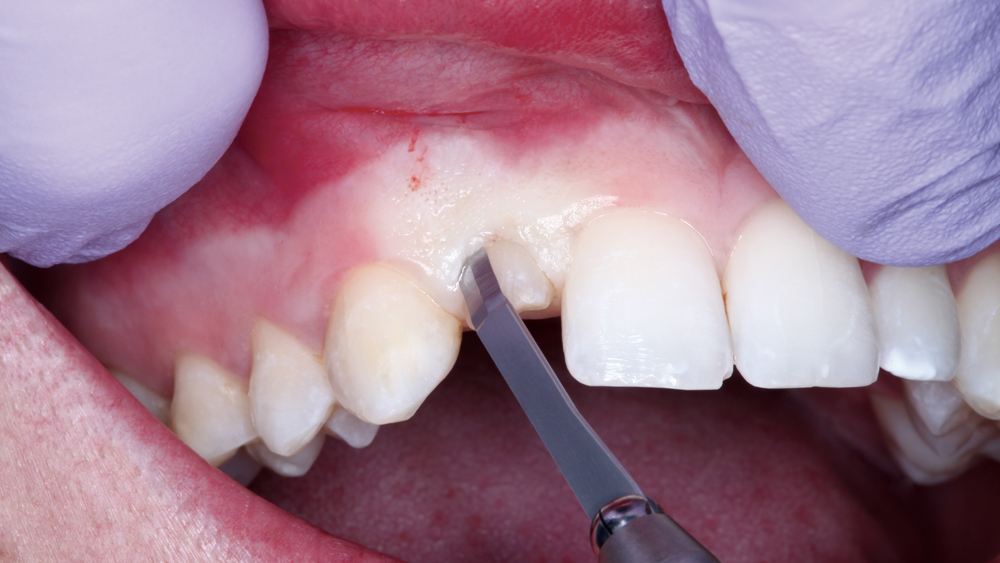

The Hahn Guided Surgical Kit (Glidewell Direct) has been designed to eliminate the need for drill keys, inserts or “spoons” commonly found in other guided surgery systems. The surgical kit’s efficient, straightforward sequence of drills creates an osteotomy in the exact shape, diameter and length of the prescribed implant, ensuring the implant ends up in the exact position determined by the digital treatment plan. Further, the entire surgical procedure, from the initial osteotomy to implant placement, is performed through the surgical guide. Whether using the Digital Treatment Planning service of Glidewell Laboratories or another source for surgical guides, specific guide sleeves are provided to enable practitioners to perform the entire surgical procedure with an efficient and fully guided protocol.

The following case illustrates the efficient, straightforward clinical workflow for placing Hahn Tapered Implants via guided surgery. A digital treatment plan is developed in which a 3.5 mm implant is positioned to support the ideal prosthetic outcome. An immediate provisional crown is designed in concert with the surgical guide and delivered at the time of surgery, helping to produce a predictable, highly esthetic restoration for a demanding case in the smile zone.